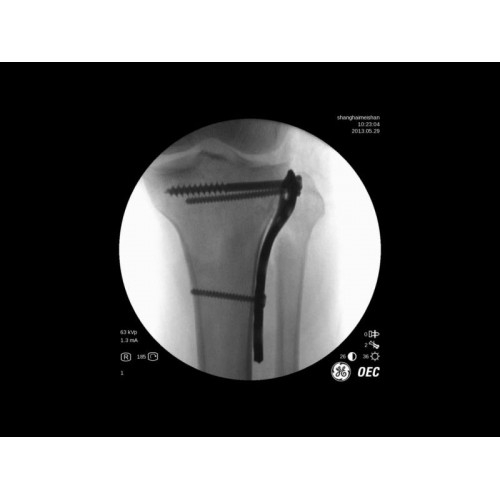

- Ортопедические операции

В практической работе GE Brivo OEC 785/865 демонстрирует стабильно высокое качество визуализации, что особенно важно при проведении сложных малоинвазивных вмешательств. Оборудование позволяет сократить время процедуры и повысить ее безопасность для пациента. Многие хирурги отмечают удобство работы с системой и ее надежность в интенсивной эксплуатации.